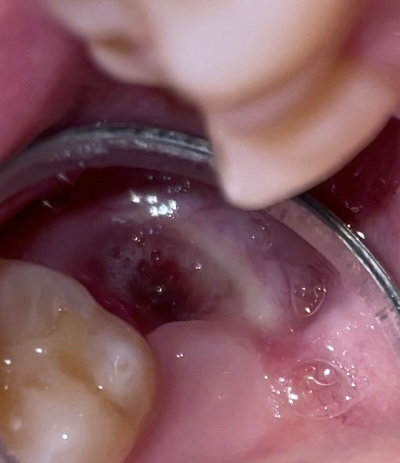

사랑니 2주 빨때 사용후 시림 즌상 (사진첨부 주의)

사랑니 발치 2주 지났는데 커피 빨때 사용하다가 갑자기 위쪽 발치한 곳이 이상한 느낌나고 살짝 시려요...

사진상 보시면 상태 어떤가요...?

사진상으로 보아 정상적으로 아물고 있는 것으로 보입니다. 2주 밖에 안되었으니 자극이 가면 불편할 수도 있지만 시간이 지나면 점점 좋아집니다.

사진 상으로는 회복이 정상적으로 이뤄지고 있습니다. 다만 발치와를 보았을 때 아직 회복이 덜 되어 있어 앞쪽 어금니에서 나타나는 시린 증상일 가능성이 큽니다. 시간이 지나면 뼈도 회복되고 잇몸도 닫힐 가능성이 매우 크므로 증상이 호전될 가능성이 큽니다. 경과를 지켜보는 것이 필요합니다.